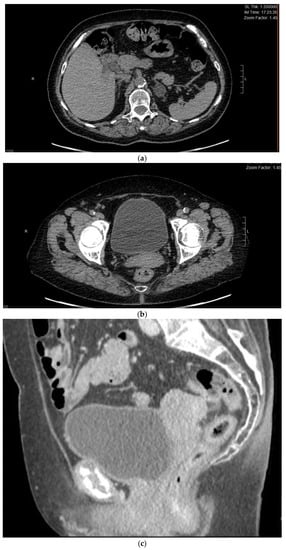

2. Case Report